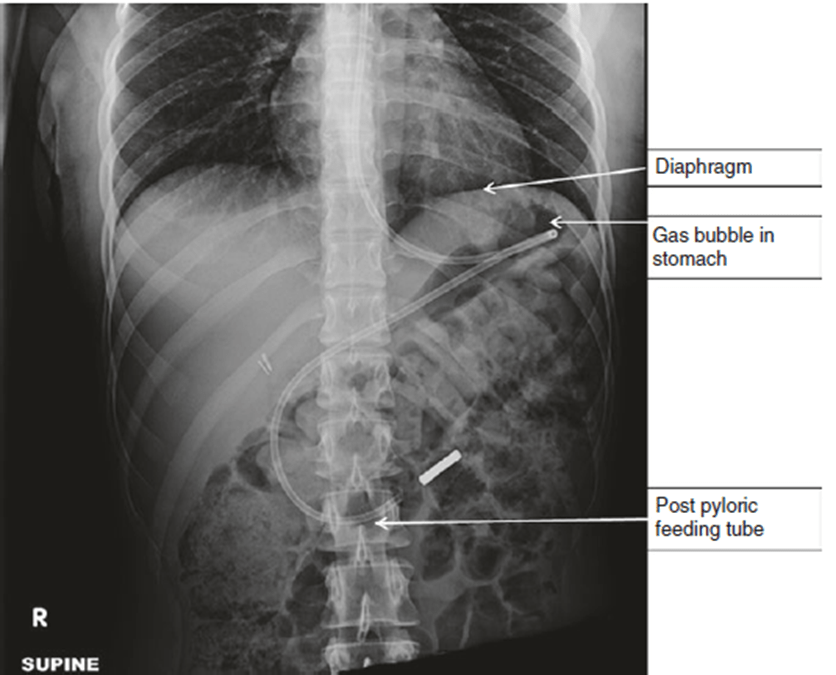

Fig. 61.1 XQ sau đặt sonde dạ dày1. Chỉ định đặt sonde dạ dày?

(f) tiêu chuẩn vàng – chụp XQ phổi và bụng để thấy toàn bộ sonde nằm trong đường tiêu hóa không có phương pháp nào chắc chắn tỷ lệ đặt sonde sai vị trí xuống còn 0% [4].

Cho đến nay, 2 “tiêu chuẩn vàng” để xác định vị trí đặt sonde dạ dày có vào đúng không: XQ và nội soi. Cả 2 đều có độ chính xác cao

Nội soi huỳnh quang giúp bệnh nhân tránh ăn tia, tuy nhiên tốn kém. Chụp XQ giúp xác định vị trí đầu ống sonde nhưng lại làm bệnh nhân phơi nhiễm bức xạ